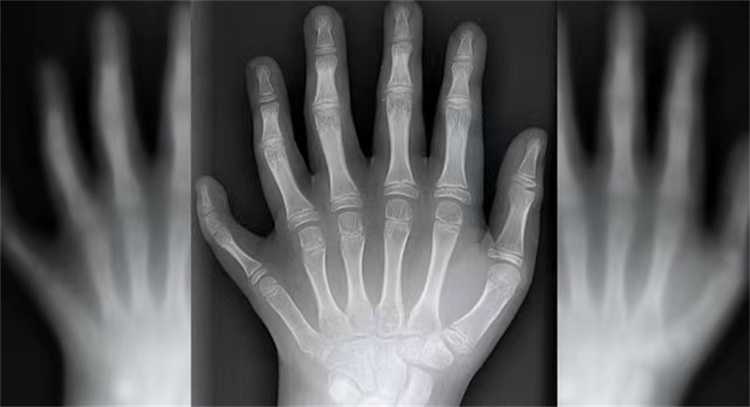

人类正常的情况下只有5根手指,只有少数人因为先天缺陷,出生后有了6根手指。如果人类出生就有6根手指,会不会加快我们做事情的效率呢?科学家认为,多一个指头并不能够让我们更加灵活,之前人类以手指计数而创造的文明,极有可能会因此而发生改变。

一直以来,出生就拥有6根手指的人,被我们认为是胚胎发育过程中出现了畸形,后期很多人也会选择手术恢复5根手指。可是我们从来没想过,如果所有的人都是6根手指,这个世界会不会因此而不一样?